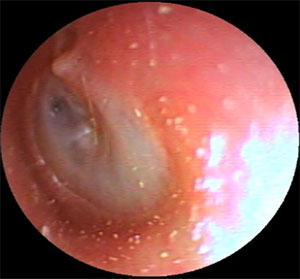

| 左外耳道炎 | ||

| 治療前 | 治療後 | |

耳だれが多い場合はバイ菌検査を行い、原因菌を調べます。

耳の中を洗浄して、患部にお薬をつけます。(抗生物質というバイ菌をやっつけるお薬を含んだ

液体や軟膏をつけます)。炎症が強い場合は飲み薬で抗生物質を内服していただく場合があります。